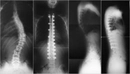

Skolyozun tanısı genellikle fizik muayene ve görüntüleme yöntemleri ile konulur.

• Fizik muayene sırasında doktor, omurganın görünümünü değerlendirir ve belirtileri inceler.

• X-ray, skolyozun derecesini belirlemek için en yaygın kullanılan görüntüleme yöntemidir.

• Gerekirse, MRI veya CT taramaları ile daha detaylı bilgi edinilebilir.

Bu yöntemler, skolyozun ciddiyetini ve tedavi gereksinimlerini belirlemede kritik öneme sahiptir.